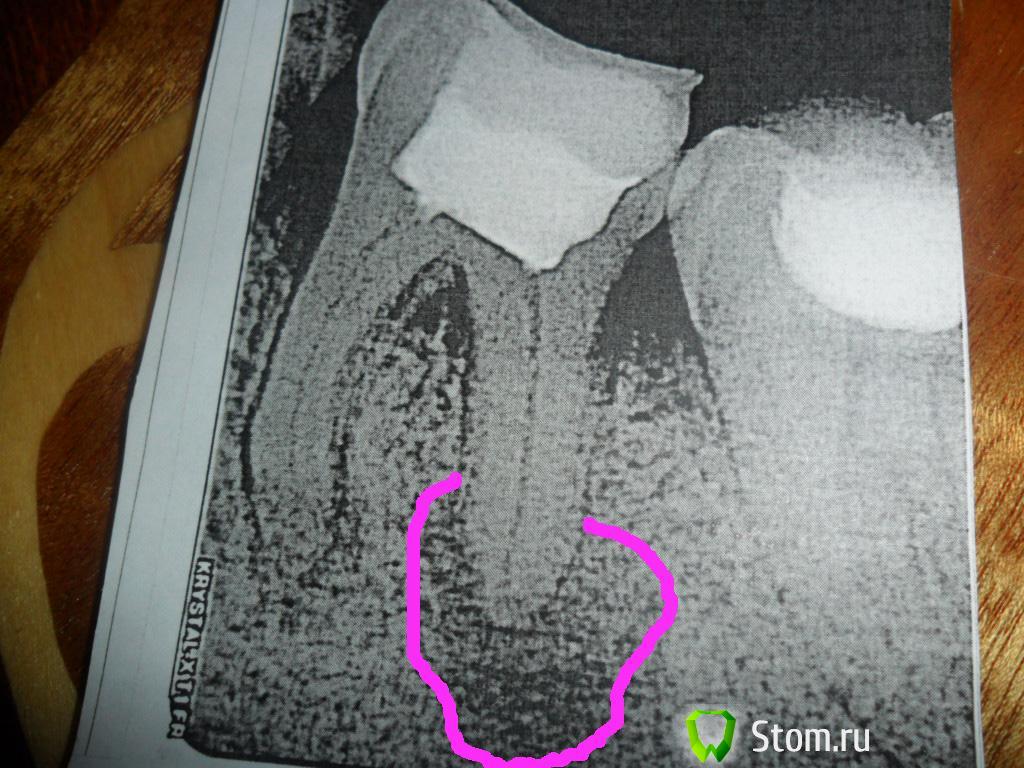

galka36 Опубликовано 6 февраля, 2012 Поделиться Опубликовано 6 февраля, 2012 Здравствуйте. несколько лет назад лечила 6 зуб снизу. Кариес был глубокий, но вот удалили нерв или нет не помню. Зуб не болел вообще, а тут на днях отломился кусок пломбы. Сам зуб не болит, а болит при надавливании, такое чувство что он вырос. Сама десна не опухла, а вот на скуле снаружи чувствую шарик при надавливании. Сегодня сделала снимок. Под корнем видно темное пятно. собираюсь идти к стоматологу. скажите пломбирование возможно или сначала нужно лечение?Что посоветуете? Можно ли по этому снимку узнать есть ли нерв в зубе?http://s43.radikal.ru/i102/1202/b2/48adbfb7ec4f.jpg Ссылка на комментарий

Salma Опубликовано 6 февраля, 2012 Поделиться Опубликовано 6 февраля, 2012 Сначала нужно лечение,у вас каналы вообше не запломбированы,около одного корня есть воспаление.Не затягивайте. Ссылка на комментарий

Salma Опубликовано 6 февраля, 2012 Поделиться Опубликовано 6 февраля, 2012 Нужно снять пломбу,прочистить,расширить,промыть антисептиком каналы(у вас там их минимум 3),запломбировать лечебной пастой,через какое то время запломбировать каналы постоянно.И периодически наблюдать за зубом, делать снимки.нервов нет,скорее всего,может частично где то в каналахСкажите,а зуб у вас обычного цвета или изменен в цвете? Ссылка на комментарий